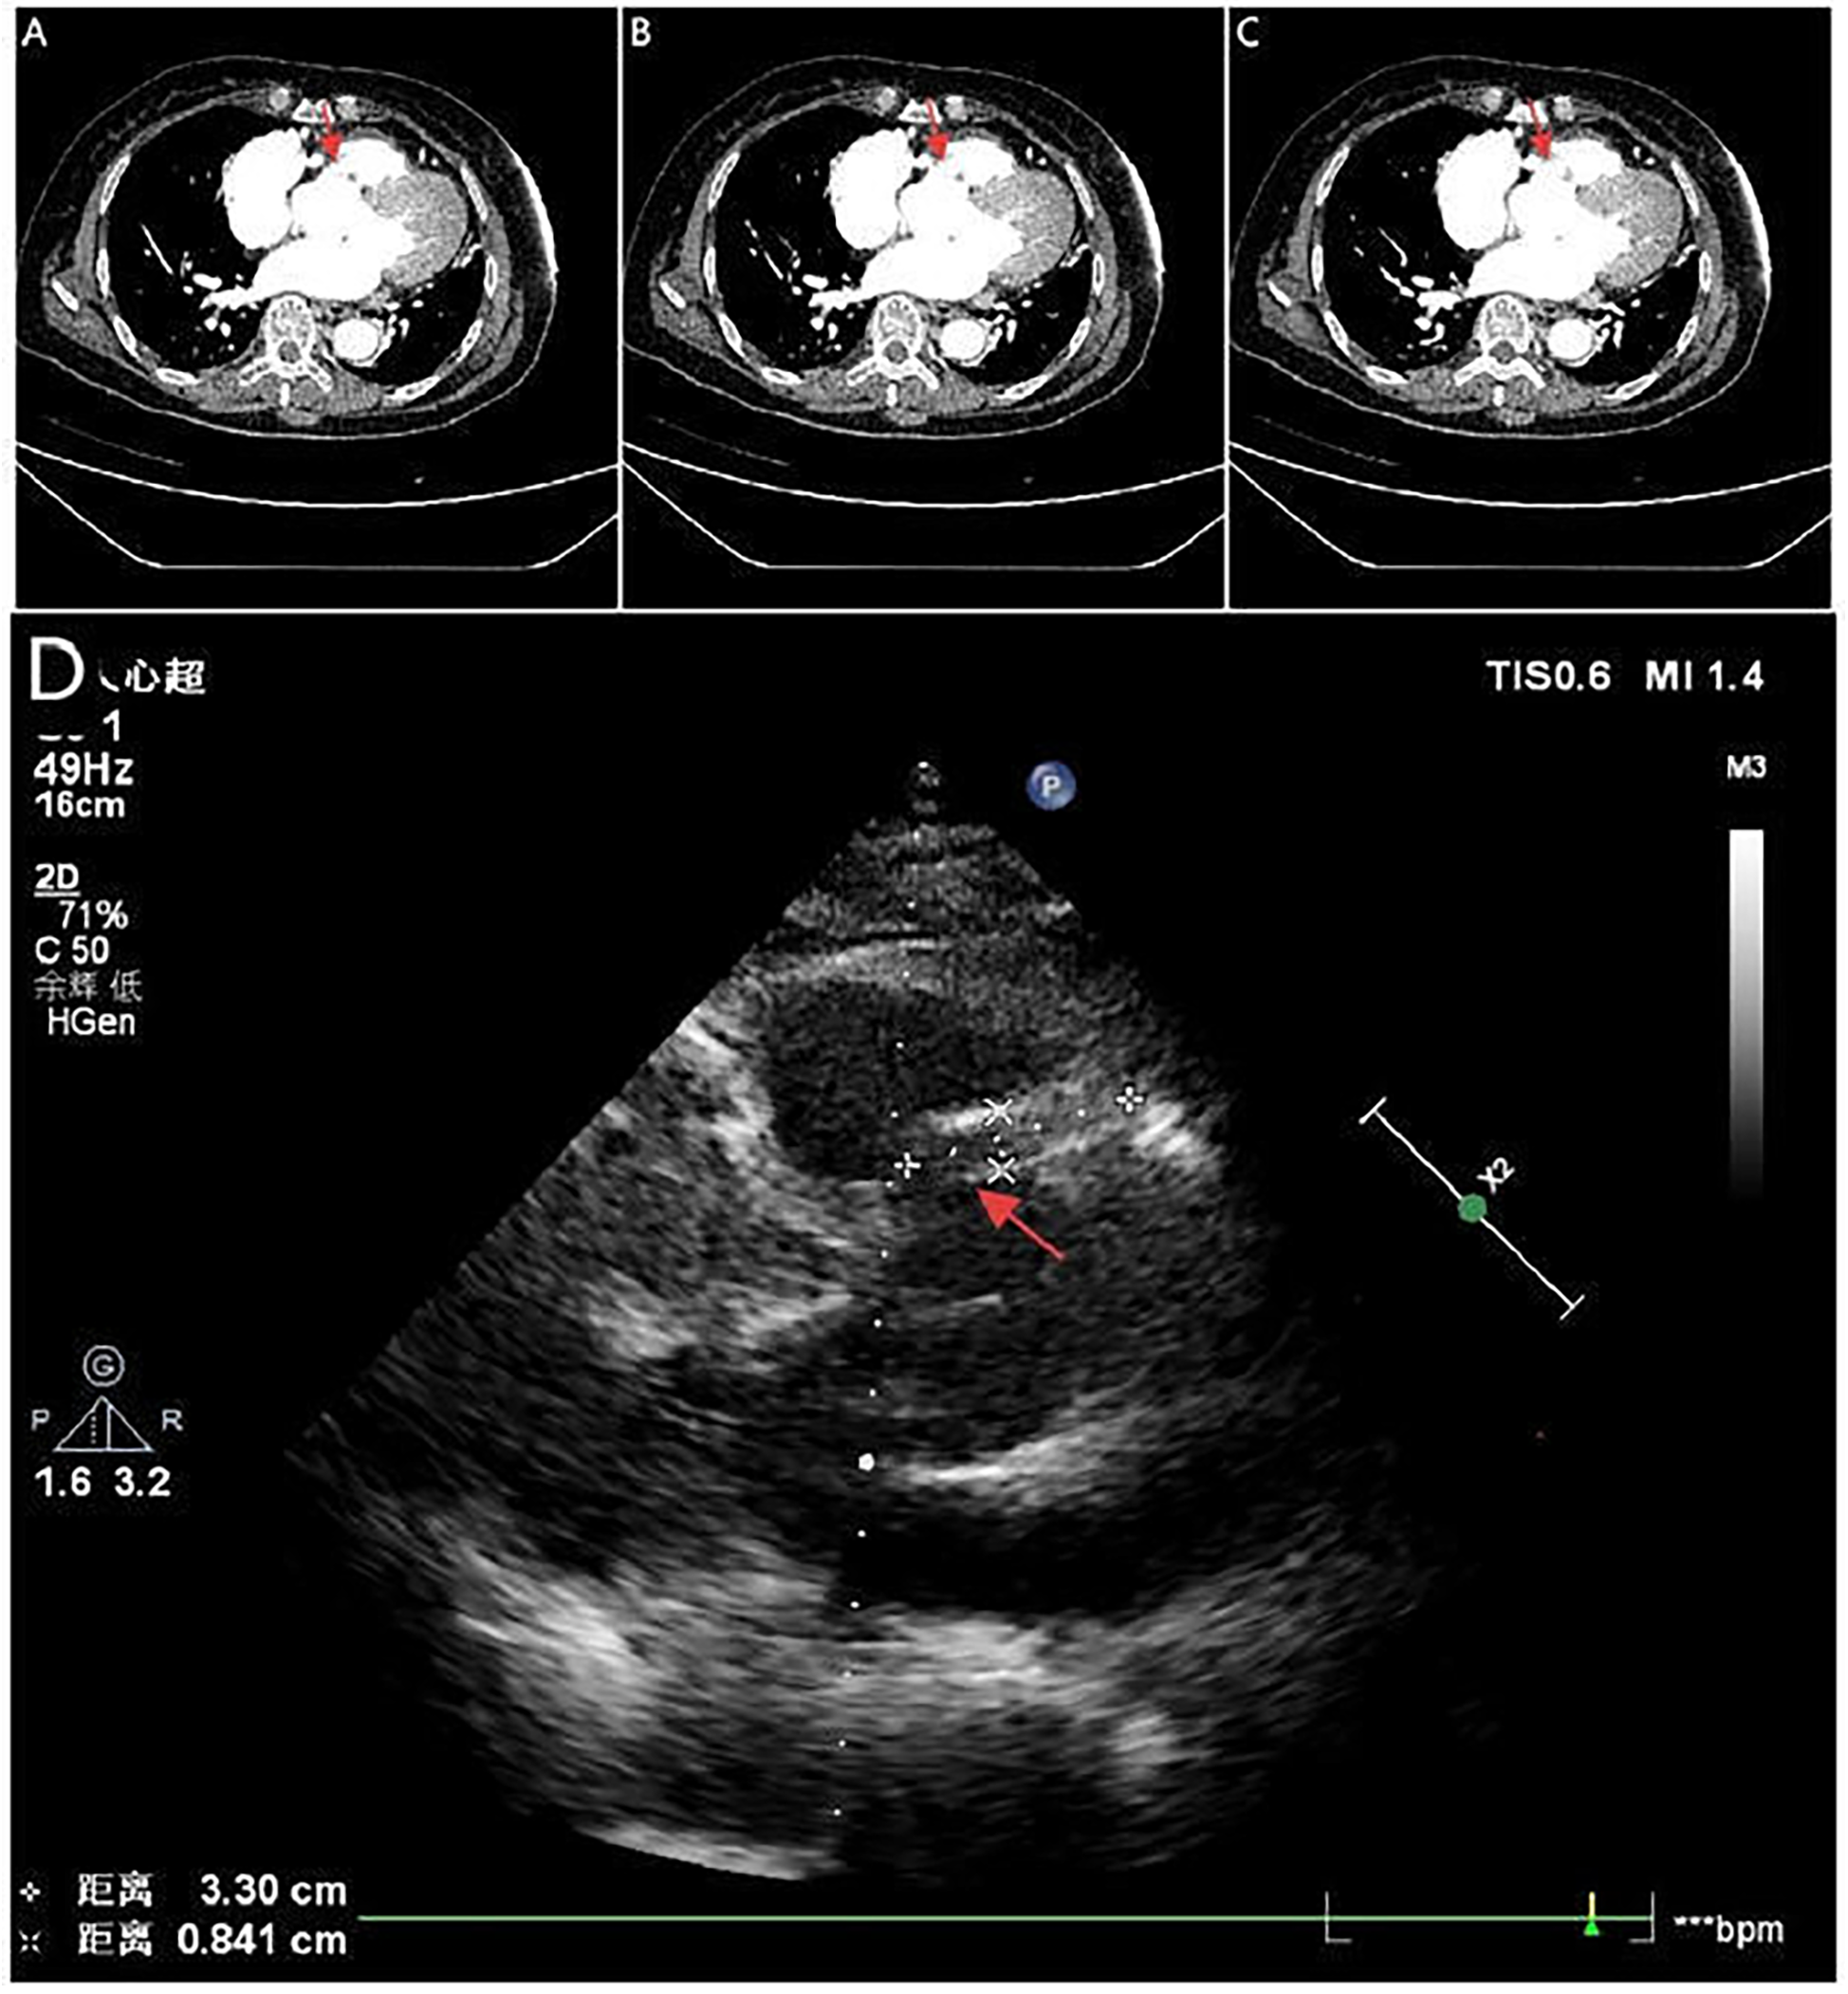

A 71-year-old woman with hypertension presented with chest tightness and diaphoresis. ECG revealed inferior STEMI and sinus bradycardia (Figure 3A). CAG demonstrated complete proximal RCA occlusion (Figures 3B–D; Supplementary Video 3) without visible intraluminal plaque on IVUS, but persistent extrinsic compression (Figures 3F–I; Supplementary Video 4). A drug-eluting stent (DES) was deployed at the ostium of the RCA with restored flow (Figure 3E). IVUS confirmed complete ostial coverage of the RCA and good stent apposition (Supplementary Video 6). CTA demonstrated mild aortic root dilation and right SOV dissection (Figures 4A–C; Supplementary Video 7). TTE demonstrated an intramural hematoma originating at the ostium of the RCA within the right coronary sinus, with partial extension into the proximal RCA (Figure 4D). The patient declined surgery and was managed conservatively. She remained stable with no recurrent symptoms during follow-up.

Figure 4

Serial CTA images (A–C) show located right coronary sinus of valsava dissection (red arrow). Echocardiography (D) demonstrates an intramural hematoma originating at the ostium of the RCA within the right coronary sinus, with partial extension into the proximal RCA (red arrow).